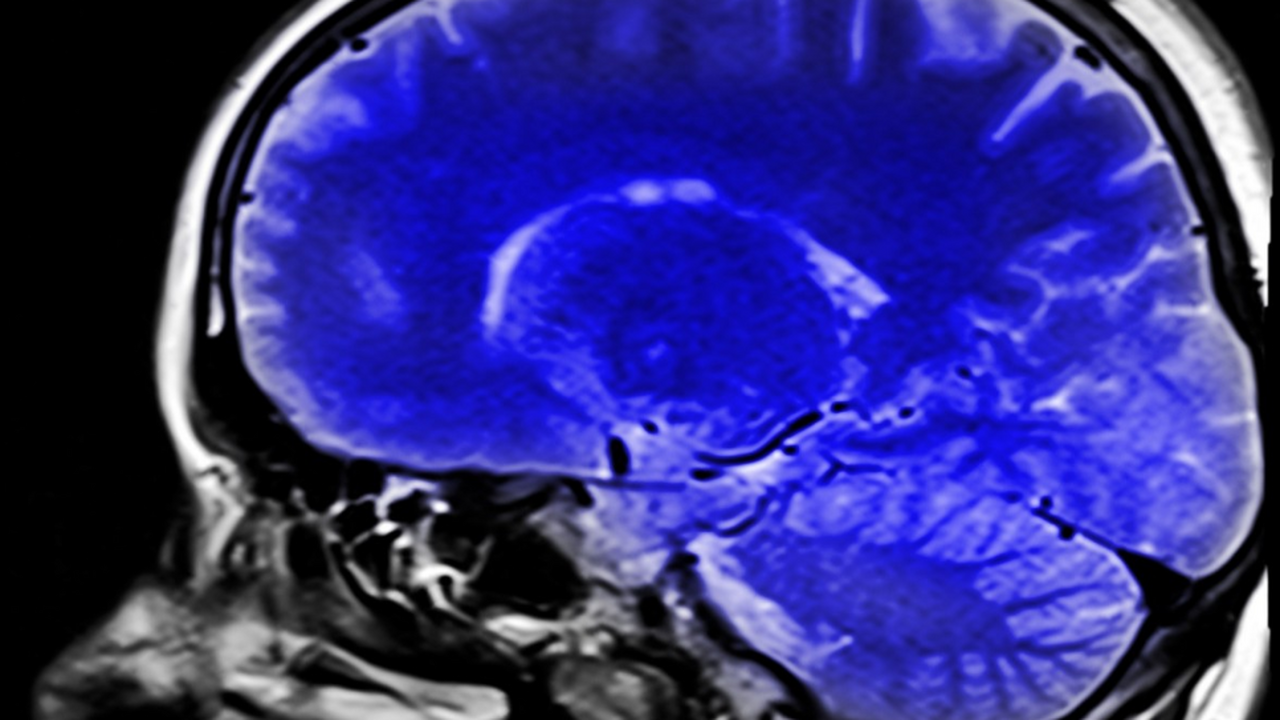

Исследователи из Weill Cornell Medicine опровергли устоявшееся мнение о том, что мозг получает энергию исключительно из глюкозы. В журнале Nature Metabolism опубликованы данные, согласно которым при активной работе нейронов они способны использовать и жирные кислоты.